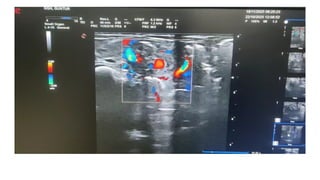

USG showing whirlpool sign of vessels which confirms

the presence of volvulus

USG showing whirlpoolsign of vessels which confirms the presence of volvulus